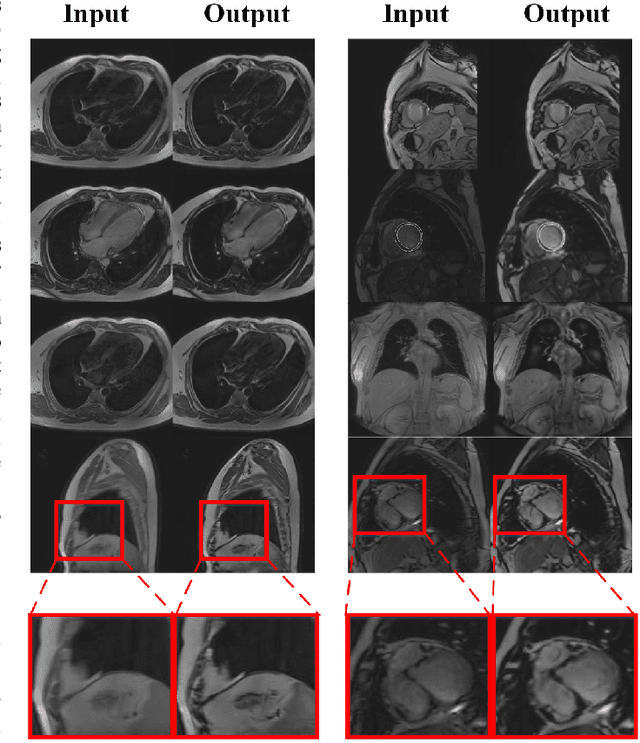

Abstract:Cardiovascular Magnetic Resonance (CMR) plays an important role in the diagnoses and treatment of cardiovascular diseases while motion artifacts which are formed during the scanning process of CMR seriously affects doctors to find the exact focus. The current correction methods mainly focus on the K-space which is a grid of raw data obtained from the MR signal directly and then transfer to CMR image by inverse Fourier transform. They are neither effective nor efficient and can not be utilized in clinic. In this paper, we propose a novel approach for CMR motion artifact correction using deep learning. Specially, we use deep residual network (ResNet) as net framework and train our model in adversarial manner. Our approach is motivated by the connection between image motion blur and CMR motion artifact, so we can transfer methods from motion-deblur where deep learning has made great progress to CMR motion-correction successfully. To evaluate motion artifact correction methods, we propose a novel algorithm on how edge detection results are improved by deblurred algorithm. Boosted by deep learning and adversarial training algorithm, our model is trainable in an end-to-end manner, can be tested in real-time and achieves the state-of-art results for CMR correction.